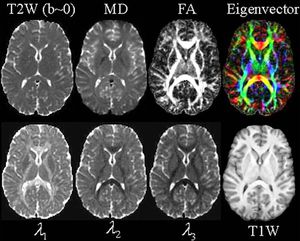

Quantitative maps from a #DTI experiment. The images include the T2-weighted (T2W) “reference” (or b=0) image from DTI data; the mean diffusivity (MD - note similar contrast to T2W image with CSF appearing hyperintense); fractional anisotropy (FA - hyperintense in white matter); the major eigenvector direction indicated by color (red = R/L, green = A/P, blue = S/I) weighted by the FA (note that specific tract groups can be readily identified); the major, medium and minor eigenvectors (11, 12, and 13, respectively). A conventional T1-weighted (from a 3D MP-RAGE) at the same anatomical location is also displayed. #MRI